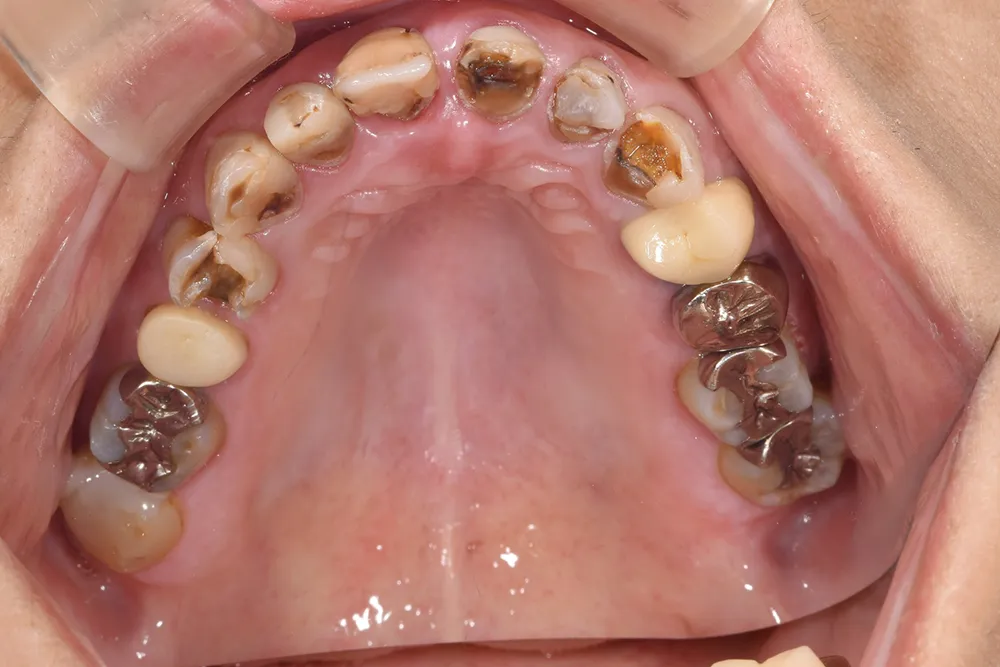

主訴 全体の審美性を高めたい

治療方法 全顎をオールセラミック補綴で治療

治療期間 約2年

通院回数等 40回

費用 4,004,000円(税込)

リスク・副作用 色調を合わせるのが難しい